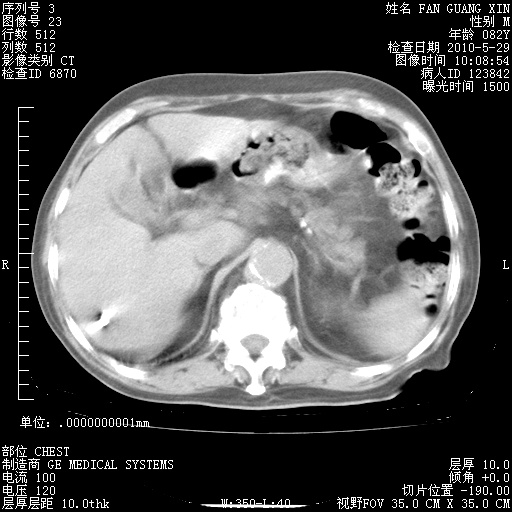

治疗3周后的肺部CT纵隔窗

再治疗10天后的肺部CT

再治疗10天后的肺部CT 纵膈窗

阅读此次胸部CT,肺间质渗出性改变较入院时有吸收。目前从体温、白细胞、中性分叶明显增高,肯定存在细菌感染(发生医院感染哦,若无消化道及泌尿系统等感染的依据,肺部感染可能大)。若你院头孢哌酮舒巴坦钠耐药率较高,同意你的方案,若48小时体温仍高,可考虑使用碳青霉稀类抗菌药物,同时可予超声雾化、注意滴数时加大液体量。白蛋白33.30g/L较低哦,需加强营养等支持治疗。